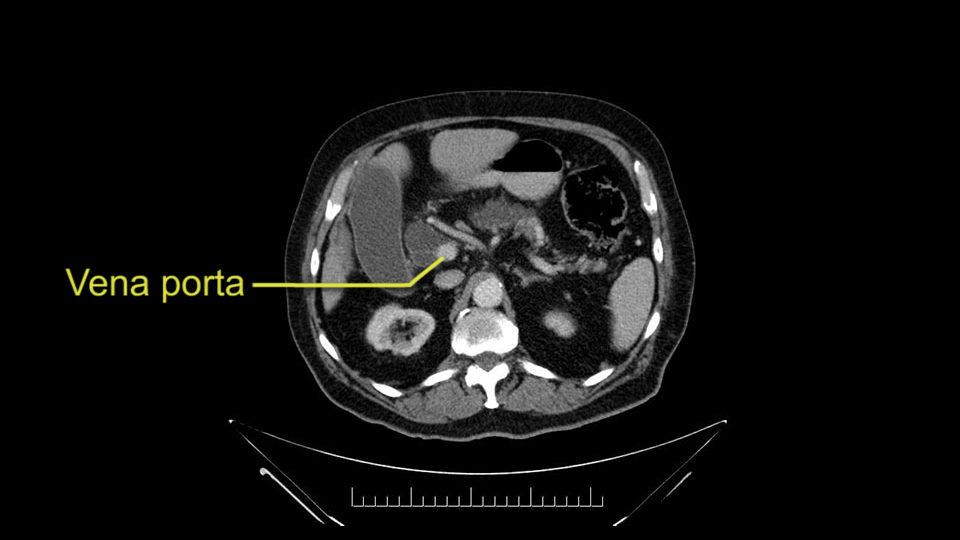

The next item that I would look at: the issue would be the vessels and usually start at the portal vein, watch the portal vein, follow it down, down-down-down to the neck of the pancreas - which is here - and there’s no impingement by tumor, which is great. The SMV and the splenic vein, which is here. The splenic vein junction is normal, which is great.

The other thing I look at is the gastroepeiploic arcade- which is this thing here- which is where the gastroepeiploic vein joins the portal vein. I call it the gateway to the neck of the pancreas because you pretty much have to divide it to get to the neck. The middle colic vein usually drains either into it or nearby. I think we’re seeing it here. Again,that can be divided and I usually divide those two and it helps me get under the neck. Again, there’s no issues here with the tumor so it’s nice from that perspective. If I was concerned about the vein, which I’m not here, I would go to the coronal view. It’s a nice way to look at the vein on just a couple of cuts and you can see a beautiful view of it here. There’s the portal vein, there’s the head of the pancreas. There’s the tumor. It’s a little closer here than it looks on the other one. I doubt it’s involved. If it’s touching, it may not be invading it but even if it was, it's a short segment. Anyways, there’s the SMV there’s the splenic vein, and everything looks good. You can see the stent. I ignore the stent. It’s the most dramatic looking thing in the picture but it’s actually the least important.

The next thing we always evaluate, although we do not expect invasion to the portal veins in this case, we must always trace the path of the portal vein, in both directions, from top to bottom. The splenoportal confluence and the superior mesenteric vein, which in this case does not appear to be compromised.

Por otro lado, siempre evaluamos -aunque en este caso no esperamos que haya invasión de los vasos portales-, siempre hay que hacer el recorrido de la vena porta, en ambos sentidos, de arriba hacia abajo; el confluente esplenoportal y la vena mesentérica superior, que en este caso no aparentan estar comprometidos.